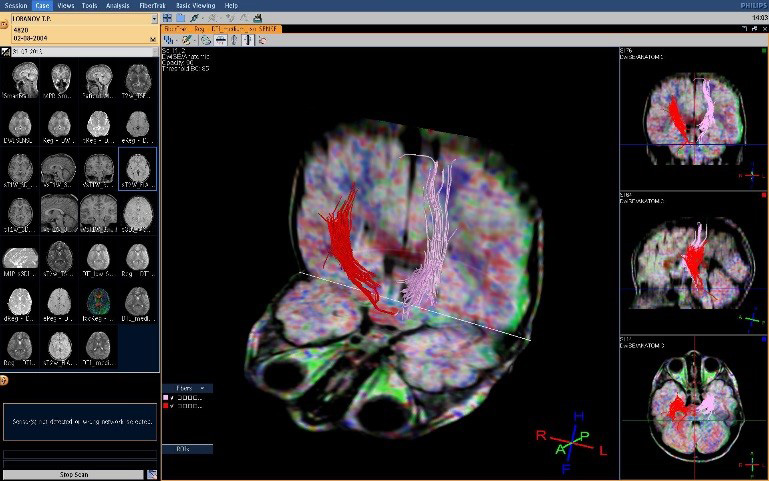

Цель: Апробация и внедрение в клиническую практику современных методик фМРТ и DTI для оценки структурных и функциональных изменений при нарушениях движения у детей. Описание проекта: Для Детского Церебрального Паралича характерно наличие незначительных структурных повреждений [1], при этом неясна их связь с нарушениями двигательных функций. фМРТ позволяет выявить зоны активации мозга при выполнении движений и оценить сложность выполнения задания по объему зон активации (Рис 1). МР-трактография позволяет исследовать структуру и диффузионные характеристики проводящих путей мозга (Рис 2). МР-волюметрия также позволяет оценить объем основных структур мозга и выявить аномалии развития, кортикальные дисплазии и патологии белого вещества мозга (Рис 3.). Результаты: Проведена клиническая апробация предложенных методик. Результаты представлены на медицинских неврологических конгрессах.

Рис 2.А.– автоматическая сегментация и рассчет объемов структур мозга по данным МРТ позволяет локализовать и оценить повреждения белого и серого вещества мозга.

Рис 2.B. – МР – трактография: выраженная ассимитрия кортико-спинальных трактов.